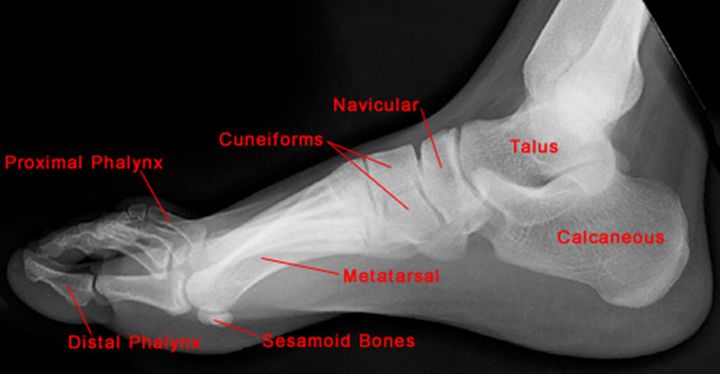

正常足侧位片

疼痛科怎么理疗疼痛科医生、康复理疗科医生、针刀针灸医生应掌握的常见骨科疾病X光片_https://www.jmylbn.com_新闻资讯_第42张